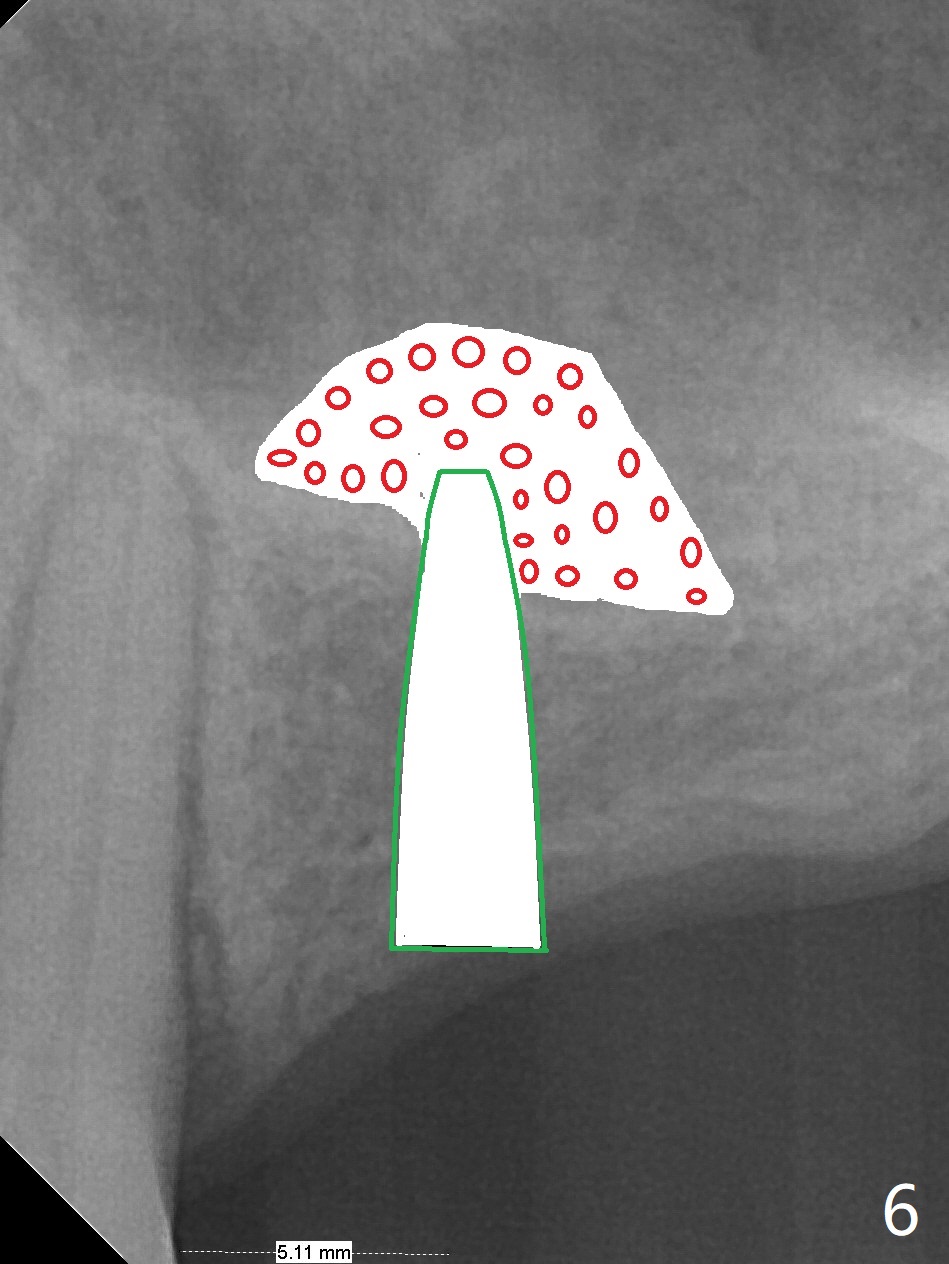

A 57-year-old woman has lost #14,15 and 18 for a while (Fig.1). Because of fear, an implant will be placed at #14 first (Fig.2). After use of Magic Drill for 5 mm (Fig.3), Magic Lifter will be used for lift (Fig.4). Following placement of PRF membrane (Fig.5 blue) and Vanilla Graft (red circles), a dummy implant is placed for additional lift (Fig.6 green). With placement of a larger and probably longer definitive implant, the graft may migrate distal due to gravity in sleep (Fig.7 arrow). In a few months, the bone height at #15 may increase to facilitate implant placement at #15.